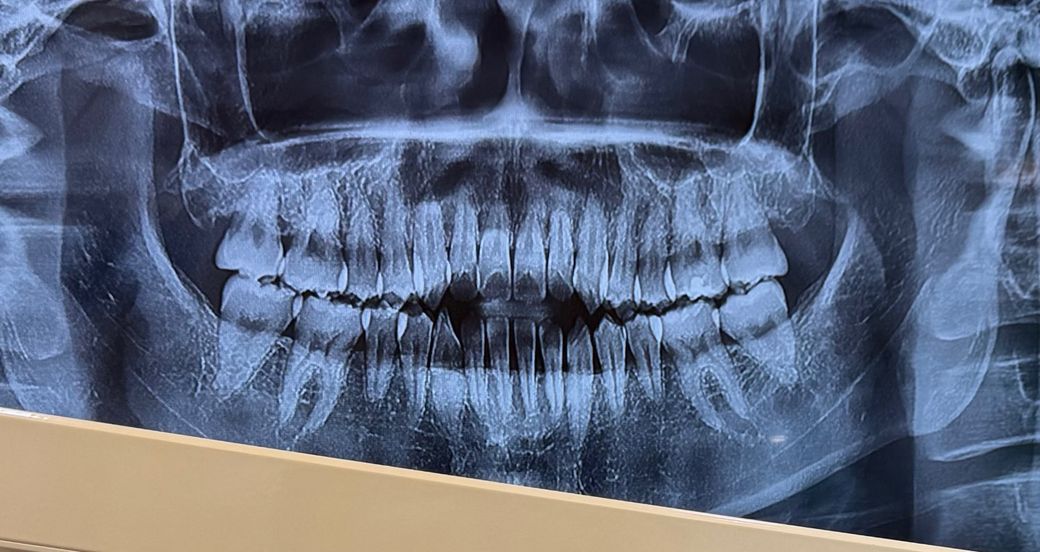

파노라마로 찍은 치아상태 어때보이나요?

오늘 치과가서 치아시림으로 치료를 받았고 나머지 치아도 충치 있는지 봐달라 말씀드렸는데 파노라마를 찍었는데도 육안으로만 확인하시더라구요 그래서 그럼 충치는 없는거죠?라고 여쭤보니 없다 하시는데 육안으로 확인하신거라 인접면충치와같은 세밀한부문의 충치가 있을까 제가 좀 불안해서 다른분께 여쭤보니 사진을 보신 다른 치과의사분은 치아가 깨져있을 가능성도 있고 작은 충치도 있을수 있을것같다 하시는데 진짜 그래보이는지 확인부탁드립니다 ㅠㅠ

엑스레이 상으로는 크게 충치가 잇어 보이진 않고 잇몸도 크게 나빠보이진 않으니 걱정하지 않으셔도 될것같습니다.

사진으로 봤을 경우에 큰 충치는 없는 것으로 보입니다. 하지만 좀 더 정확하게 확인을 하기 위해서는 육안상의 확인이 필요할 것으로 생각됩니다.

파노라마 사진에서 충치는 없는 것으로 보입니다. 물론 해상도가 흐리기는 하지만 충치 없을 가능성 높습니다.

인접면 충치 등 세세한 부분은 해상도가 더 높은 작은 엑스레이사진을 찍어봐야 합니다 위 사진만으로 알 수 있다고 한다면 그건 거짓말입니다